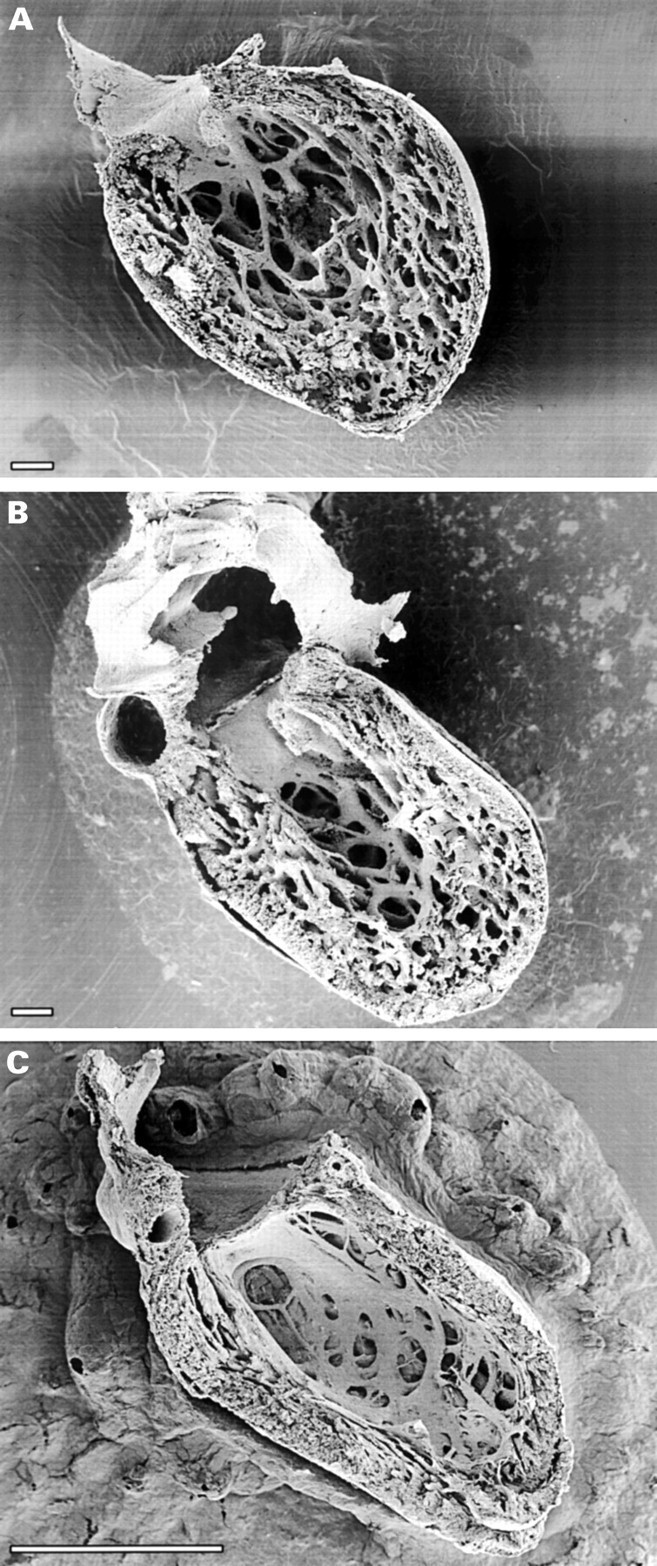

- The process of normal trabecular compaction. (A) at first six weeks of fetal life, (B) at 12 weeks and (C) completion of myocardial compaction. [Sedmera et al. Anat Rec 2000;258:319-37]